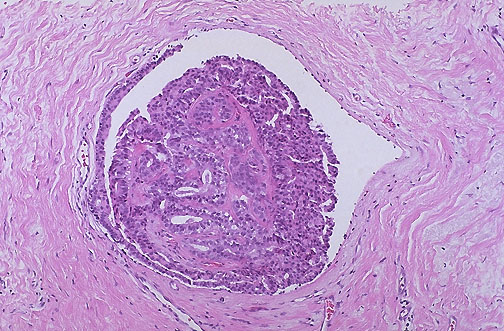

| A small benign intraductal papilloma appears here in a breast duct, typically in one of the main lactiferous ducts beneath the areola. Note that the epithelial cells show no atypia and that there is a fine pink collagenous stroma within the papilloma. An intraductal papilloma may be associated with a serous or bloody nipple discharge, or it may cause some nipple retraction. |